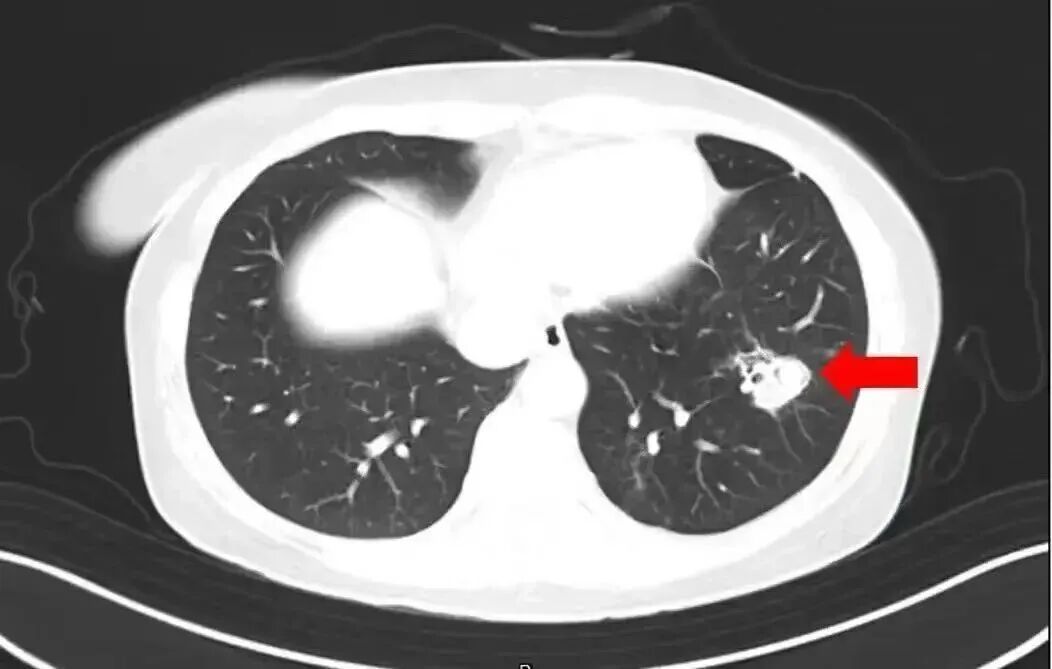

2025年1月,江苏扬州的张大爷为迎接春节开始大扫除,清扫过程中不慎吸入大量灰尘和霉菌孢子,导致哮喘发作。张大爷随即服用了常备的哮喘治疗药物,可症状反而逐渐加重。经检查,张大爷的肺部出现感染,确诊为肺曲霉病。